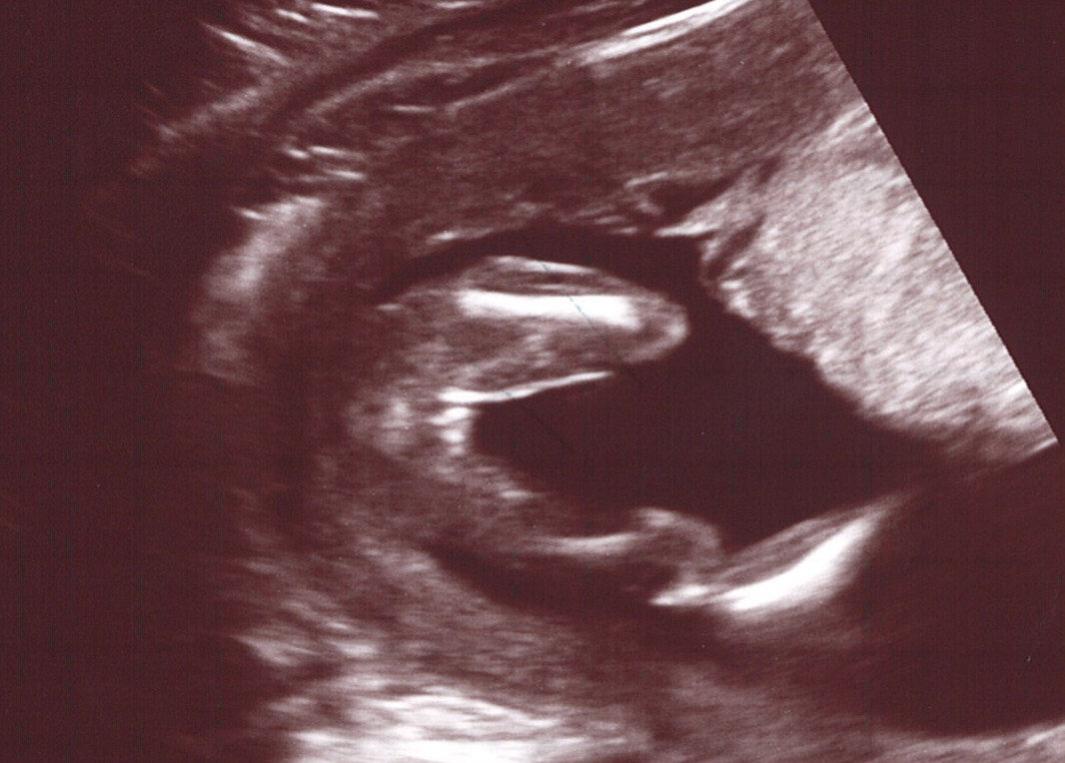

Is the 16 weeks potty shot girl or boy?? Not sure if I've attached properly!

I was just wondering if the 2 white bits between the legs could be a scrotum - but I guess it might not be as it doesn't stick out ans there doesn't seem to be a willy lol

Penises tend to "float" in the amniotic fluid which is why I think boys are much easier to see than girls sometimes. With both of my boys, it was very obvious before the tech even said anything.